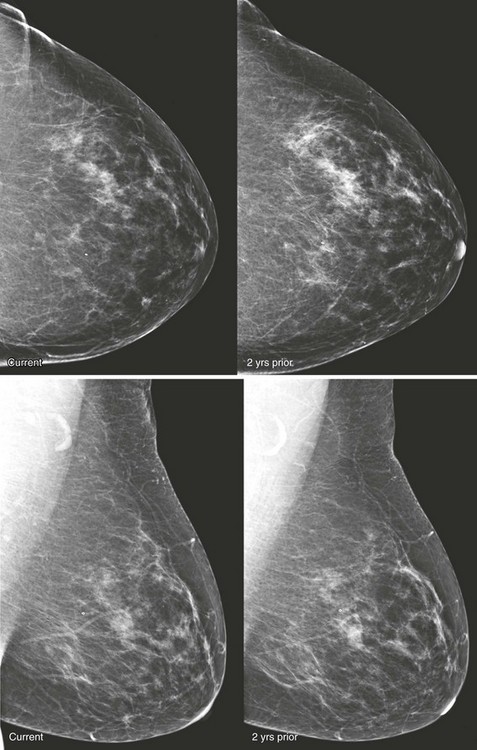

CASE 8-8. Screening mammogram on a 68-year-old woman with a comparison study from 2 years prior. What are the findings? What are your BI-RADS assessment and recommendation?

CASE 8-8. There are at least three new bilateral isodense masses with circumscribed margins (arrows). There were no masses on prior mammograms; therefore, diagnostic views and US were performed. CC spot compression views show circumscribed margins. US reveals bilateral oval solid masses. Core biopsy of masses in the 12 o’clock position of the right breast and the 10 o’clock position of the left breast both revealed previously unsuspected extranodal marginal zone B-cell lymphoma.